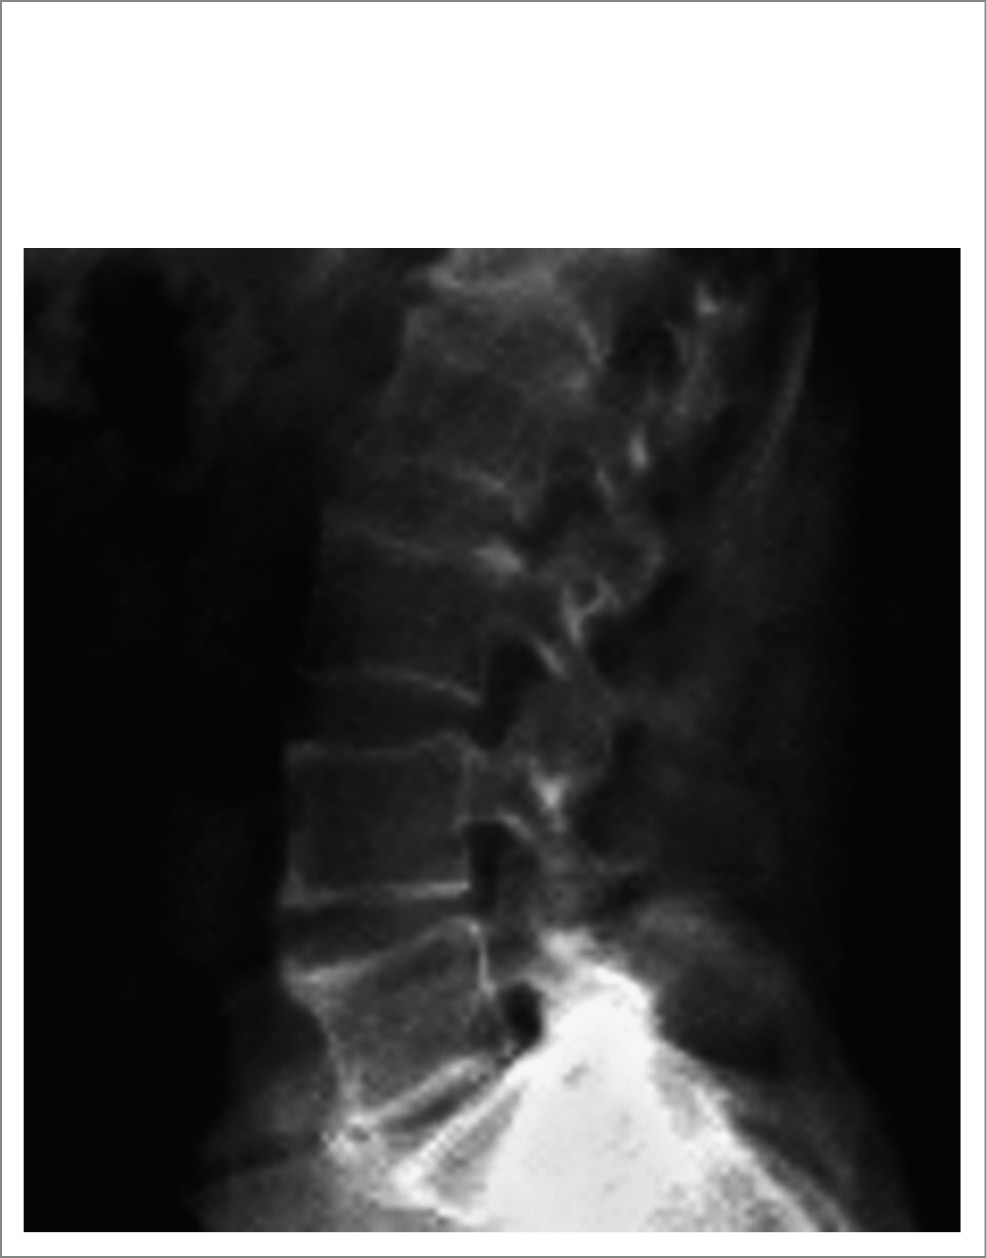

Туберкулез. Поводом для того, чтобы заподозрить туберкулезный спондилит, являются в основном особенности визуализационных изменений позвоночника (деструкция, спондилодисцит). Наиболее часто вовлекаются парадисковые отделы позвонка, что рентгенологически выражается в нарастающем сужении межпозвонкового промежутка, часто неравномерном и более выраженным спереди (на боковом снимке). Известны и другие рентгенологические варианты начала спондилита – центральный (поражается центральная часть тела), подсвязочный (под передней продольной связкой) и редкий задний тип (с поражением дужек и остростков). На МРТ находят отек КМ, первоначально не сопровождающийся дисцитом. В последующем развивается деструкция диска, а гранулематозное воспаление распространяется на соседний позвонок с формированием одного или нескольких округлых участков разрушения трабекул. Данные очаги на рентгенограмме имеют склерозированные контуры и внутри содержат секвестры округлой формы и небольших размеров, похожие на «тающий кусочек сахара». В центре секвестра выделяется более темный участок разрушающейся костной ткани, окруженный светлой каймой грануляций. Во многих случаях формируются паравертебральные и эпидуральные абсцессы (натечники). Паравертебральные абсцессы, расположенные в нижнегрудном или поясничном отделах, могут «продвигаться» по подвздошно-поясничной мышце вплоть до места ее прикрепления к малому вертелу бедренной кости. Со временем присоединяются процессы репарации с развитием остеосклероза тел, полным слиянием пораженных позвонков и окостенением связочного аппарата. Самый надежный метод диагностики – выявление микобактерий в биоптате из места поражения позвоночника, однако существуют и косвенные диагностические методы, включая внутрикожные пробы, серологические, тесты на микобактерии, проведенные методом полимеразной цепной реакции.

Спондилиты (спондилодисциты) могут вызываться и другими бактериями. Визуализационная картина в этих случаях не имеет каких-либо особенностей и не отличается существенно от туберкулезного или бруцеллезного поражения позвоночника (рис. 8).

Рис. 8. Пациентка Б., 33 года. Диагноз – остеомиелит тел позвонков LI и LII вероятно стафилококковой природы: a – рентгенограмма поясничного отдела позвоночника: деструкция смежных отделов LI и LII; b – МРТ (сагиттальная плоскость, режим Т2): дисцит в сегментах ThXII–LI и LII–LIII; c – МРТ (аксиальная плоскость, режим T2-STIR): паравертебральное жидкостное образование размерами 2,3×1 см (стрелка) в области левой подвздошно-поясничной мышцы (натечник).